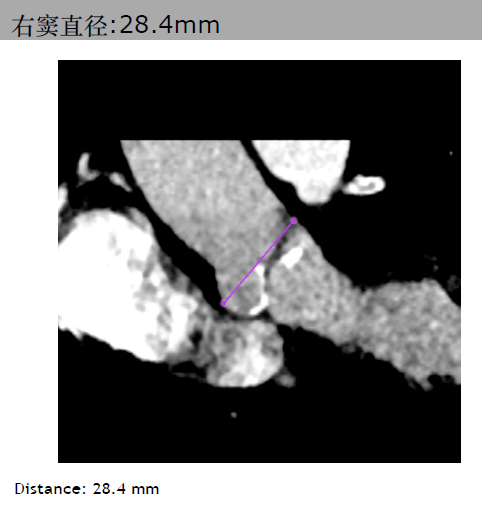

三叶瓣,主动脉瓣环平均直径21.3mm。右冠脉高度10.3mm,右窦直径:28.4mm。左冠脉高度14.1mm,左窦直径:30.4mm。STJ平均直径25.4mm,高度17mm。